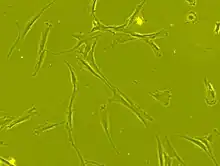

Stem cell transplantation is an important avenue for SCI research: the goal is to replace lost spinal cord cells, allow reconnection in broken neural circuits by regrowing axons, and to create an environment in the tissues that is favorable to growth.[76] A key avenue of SCI research is research on stem cells, which can differentiate into other types of cells—including those lost after SCI.[76] Types of cells being researched for use in SCI include embryonic stem cells, neural stem cells, mesenchymal stem cells, olfactory ensheathing cells, Schwann cells, activated macrophages, and induced pluripotent stem cells.[162] Hundreds of stem cell studies have been done in humans, with promising but inconclusive results.[149] An ongoing Phase 2 trial in 2016 presented data[163] showing that after 90 days, 2 out of 4 subjects had already improved two motor levels and had thus already achieved its endpoint of 2/5 patients improving two levels within 6–12 months. Six-month data is expected in January 2017.[164]

In 2014 Darek Fidyka underwent pioneering spinal surgery that used nerve grafts, from his ankle, to 'bridge the gap' in his severed spinal cord and olfactory ensheathing cells (OECs) to stimulate the spinal cord cells. The surgery was performed in Poland in collaboration with Prof. Geoff Raisman, chair of neural regeneration at University College London's Institute of Neurology, and his research team. The OECs were taken from the patient's olfactory bulbs in his brain and then grown in the lab, these cells were then injected above and below the impaired spinal tissue.[169][170]